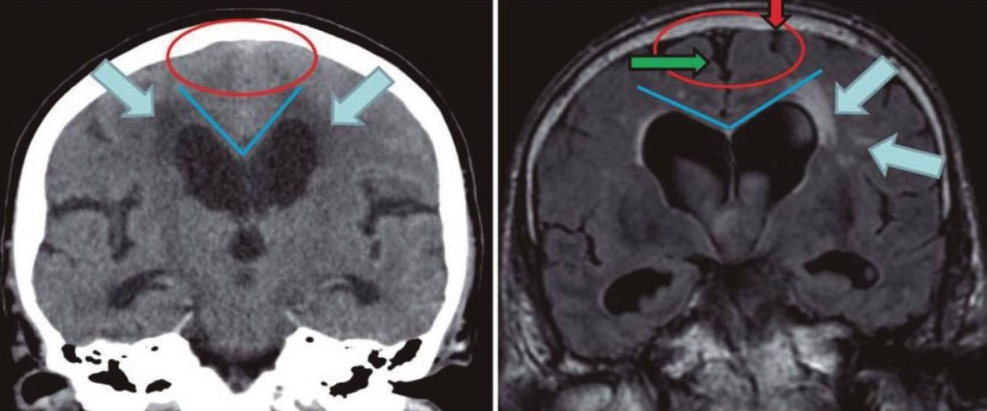

뇌척수액은 뇌 안쪽에 있는 뇌실에서 만들어져 척수 주변 지주막하 공간을 순환하고, 뇌 아래 지주막하 공간을 지나 대뇌 표면 지주막하 공간으로 모인 후, 양 대뇌 반구 사이 상시상 정맥동 안으로 흡수되어 혈액으로 되돌아가며 순환합니다.

그런데, 어떠한 원인에 의해 뇌실 내 뇌척수액의 순환로 일부가 막히면 뇌척수액이 두개강이나 척추강에 비정상적으로 축적이 되는데, 대부분의 경우 뇌압 상승으로 이어지며 이로 인한 증상과 뇌 발달의 장애를 일으키며, 뇌압이 급격히 상승할 경우, 생명에 위협을 줄 수도 있습니다.

뇌실이 급격히 확장하게 되면 두통, 오심, 구토, 시신경 유두 부종, 졸림, 코마 등의 증상을 보일 수 있고, 압력이 증가한 부위가 인접 부위 뇌를 밀어서 뇌간에 압력을 가하는 위험한 상황이 벌어질 수도 있습니다.